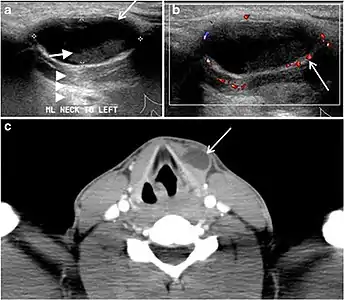

Fig. 7. A 51-year-old female patient post total thyroidectomy for PTC with elevated thyroglobulin measurement. an Axial non-enhanced CT scan of the neck at the level of the thyroid bed demonstrates a well-defined, rounded, homogenously dense soft tissue situated between the trachea and left internal jugular vein (white arrow). b Transverse ultrasound image of the neck demonstrates a well-defined, homogeneous, hypoechoic soft tissue nodule measuring 6 mm (white arrow) with no detected micro-calcifications. Biopsy showed a predominantly residual normal thyroid tissue with micro-foci of PTC.[1]